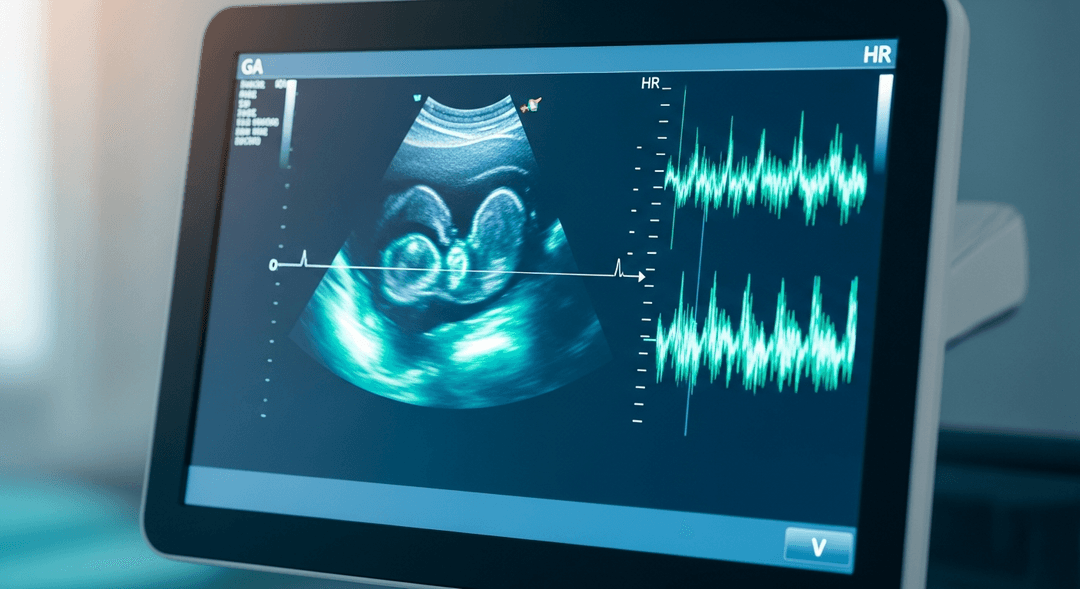

Surveillance échographique

Lors de l'échographie, l'échographiste peut visualiser le cordon autour du cou et évaluer son impact :

- Visualisation en mode B (image classique)

- Confirmation par Doppler couleur (flux sanguin)

- Vérification que le cordon n'est pas serré (flux normal)

- Évaluation de la quantité de liquide amniotique